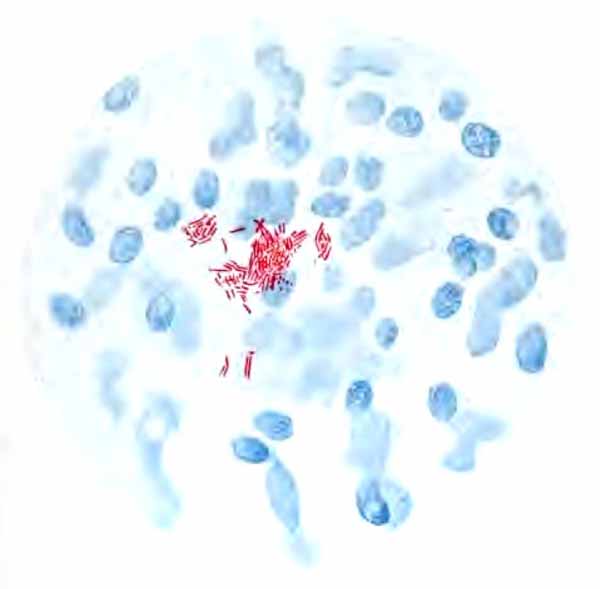

In films stained by Gabbet's method tubercle bacilli, if present, will be seen as slender red rods upon a blue background of mucus and cells (Plate II, Fig. 2). They average 3 to 4 µ in length—about one-half the diameter of a red blood-corpuscle. Beginners must be warned against mistaking the edges of cells, or particles which have retained the red stain, for bacilli. The appearance of the bacilli is almost always typical, and if there seems room for doubt, the structure in question is probably not a tubercle bacillus. They may lie singly or in groups. They are very frequently bent and often have a beaded appearance. It is possible that the larger, beaded bacilli indicate a less active tuberculous process than do the smaller, uniformly stained ones. Sometimes they are present in great numbers—thousands in a field of the one-twelfth objective. Sometimes several cover-glasses must be examined to find a single bacillus. At times they are so few that none are found in stained smears, and special methods are required to detect them. The number may bear some relation to the severity of the disease, but this relation is by no means constant. The mucoid sputum from an incipient case sometimes contains great numbers, while sputum from large tuberculous cavities at times contains very few. Failure to find them is not conclusive, though their absence is much more significant when the sputum is purulent than when it is mucoid.

PLATE II

Heart-failure cells in sputum

FIG. 1.—Heart-failure cells in sputum, containing blood-pigment, from a case of cardiac congestion of the lungs (Jakob).

Sputum showing tubercle bacilli

FIG. 2.—A, Sputum showing tubercle bacilli stained with carbol-fuchsin and Gabbet's methylene-blue solution (obj. one-twelfth oil-immersion); B, sputum of anthracosis, showing particles of coal-dust stained with methylene-blue (obj. one-twelfth oil-immersion) (Boston).